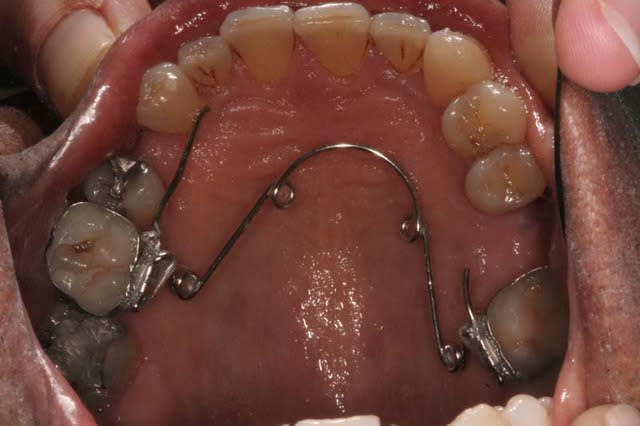

Je peux alors mettre un arc Inf.

Cas terminé